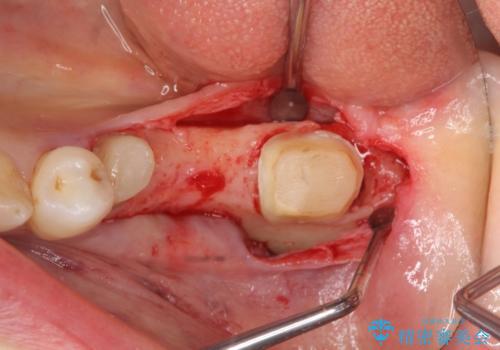

左下7の遠心部は部分的な骨欠損によるポケットが10mmあったため、再生療法による骨の再生を行いました。

再生療法とは歯槽骨の欠損部位を人工骨で補うことにより骨を再生させる手術です。

この手術を行うことで、歯周基本治療では治癒しない歯周病を改善したり、本来ならば抜歯しなければならない歯を保存することができます。